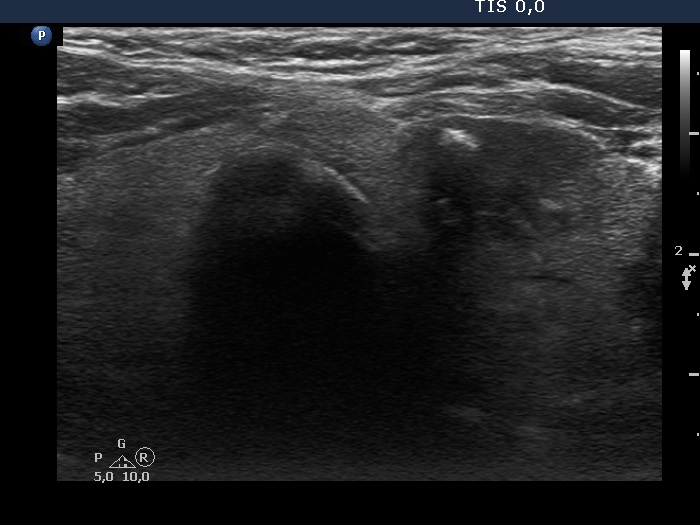

Clinical presentation: On evaluation of weight loss, a multinodular goiter was found in an 85-year-old woman.

Palpation: a firm nodule in the left lobe.

Ultrasonography. The thyroid was echonormal and beside has small hypoechogenic areas, had two nodules. Both were hypoechoic. The lesion in the left lobe presented different intranodular hyperechogenic figures including macrocalcifications and comet-tail artifacts. Some granules were probably microcalcifications.